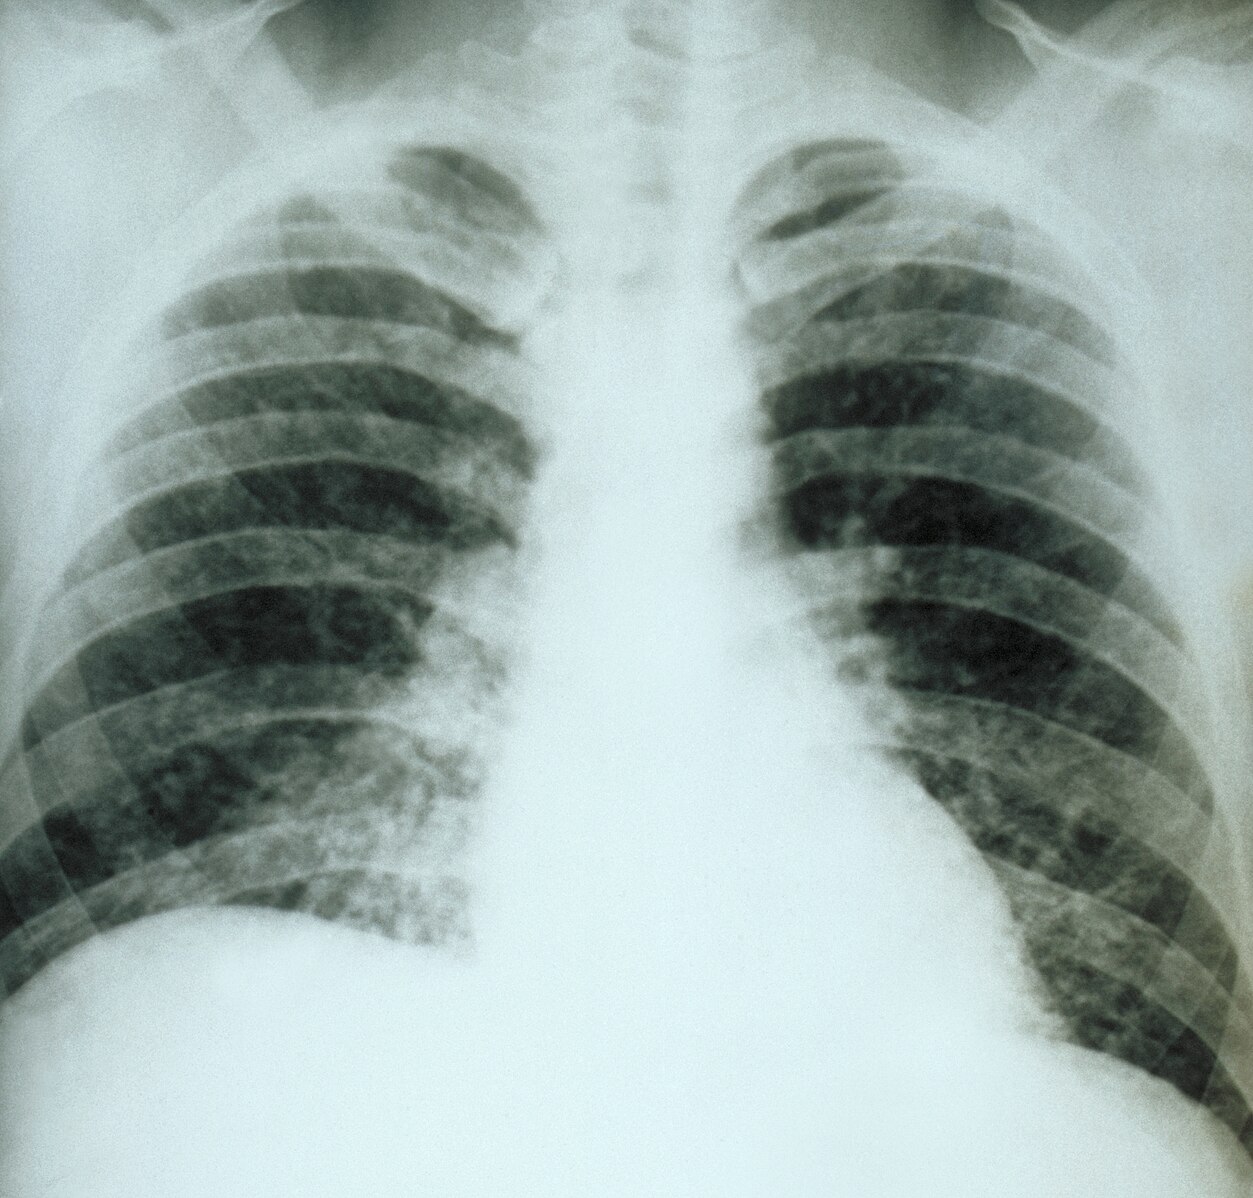

- X-rays

Chest X-ray (Acute Pulmonary Histoplasmosis).